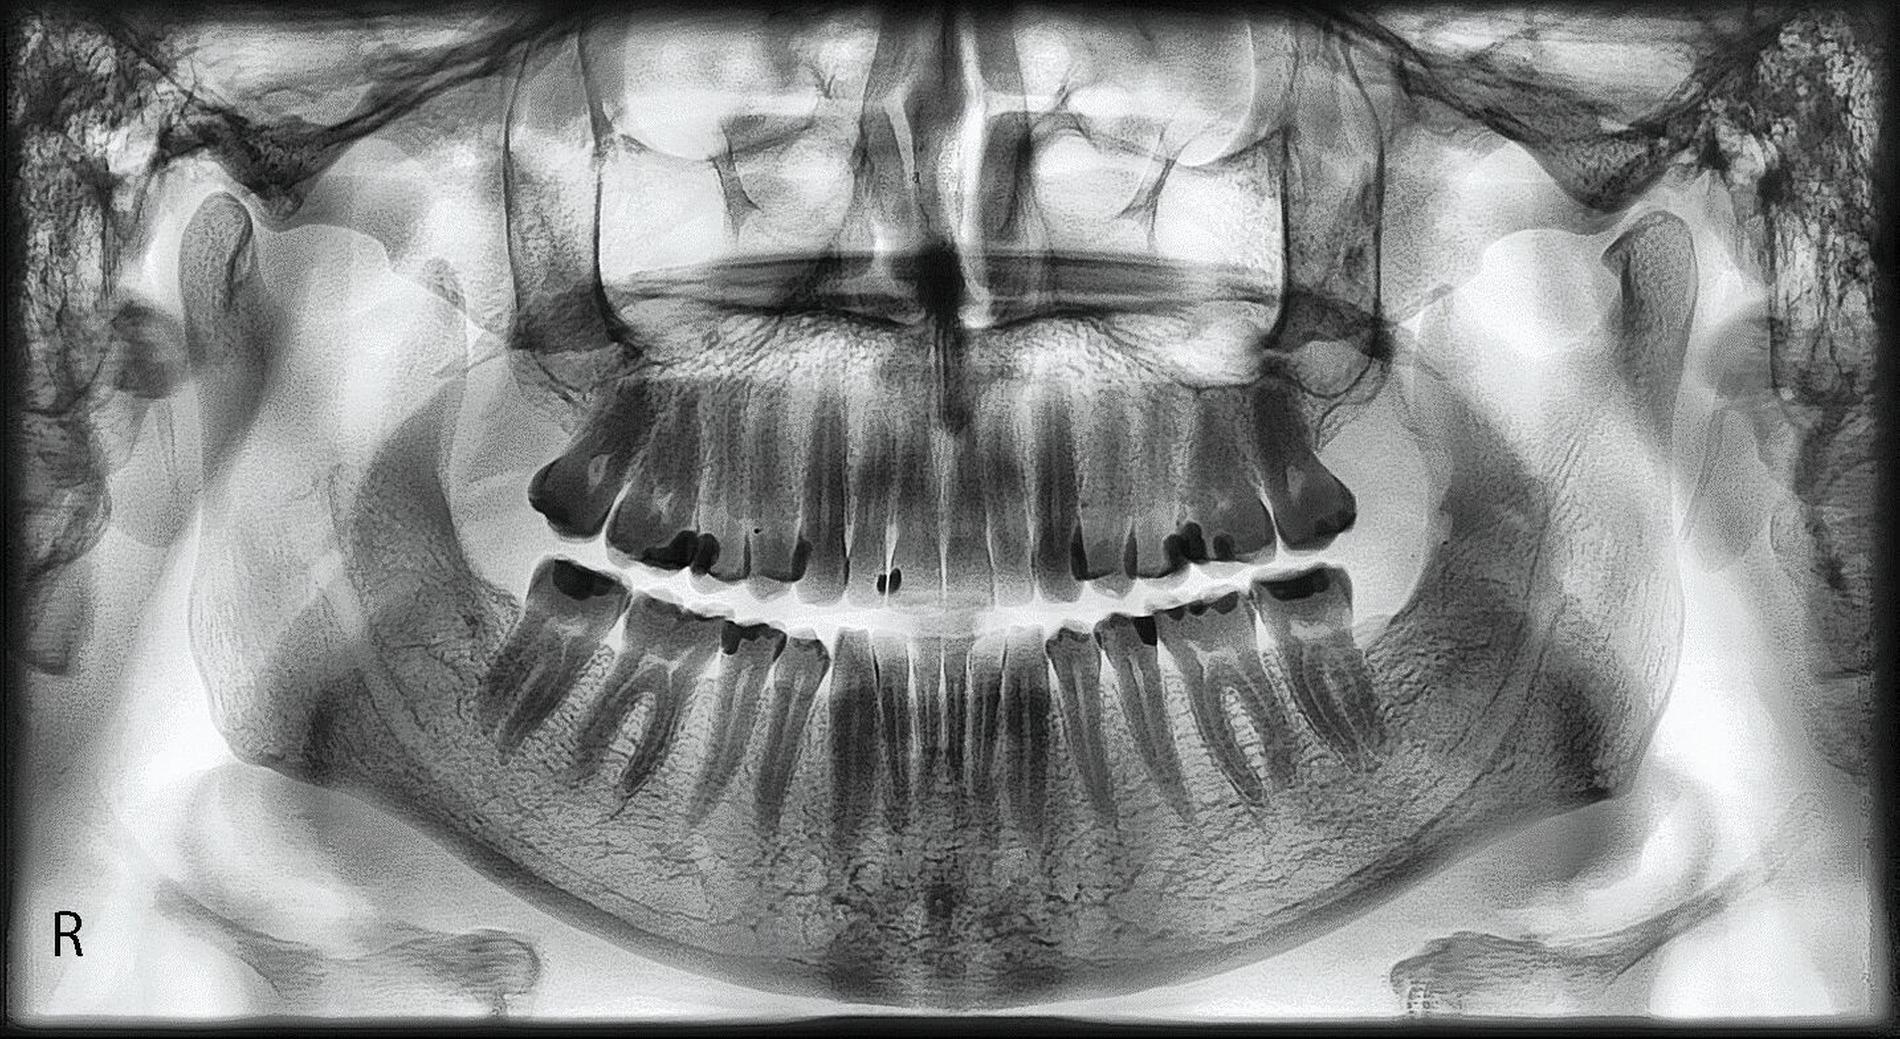

Radiologische Befundung

Auf der Panoramaschichtaufnahme sind aus funktioneller Sicht vor allem die Kiefergelenke und die Kieferwinkel von besonderem Interesse [Türp et al., 2016; Türp et al., 2021; Simonek et al., 2024]: Die mit langjährigem Kieferpressen einhergehenden funktionellen Belastungen (hohe Beißkräfte bei lang anhaltender Kontraktion der Kieferschließer) können zu knöchernen Anpassungen führen, die als biologische Remodellierung zu interpretieren sind. Diese äußern sich auf der Panoramaschichtaufnahme in folgenden Befunden:

Kondylus beziehungsweise Tuberculum articulare: Knochenresorption (glatte Abflachung); Grund: Druckbelastung im Bereich der artikulierenden Flächen des Kiefergelenks (Abbildung 1),

Kieferwinkelbereich: Knochenapposition; Grund: Zugbelastung durch die dort ansetzenden Sehnen des M. masseter und des M. pterygoideus medialis (Abbildungen 1 und 2).

Ferner lässt das Röntgenbild einen Eindruck über den Grad der Attrition beziehungsweise Abrasion der Zähne zu, aber diese Einschätzung lässt sich klinisch genauer vornehmen.